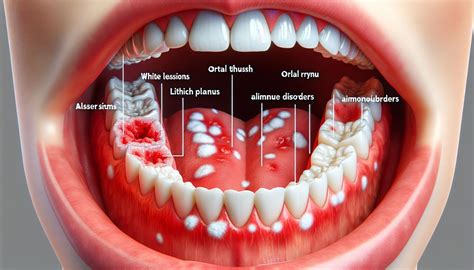

The causes of inside of mouth peeling can be varied and may include both minor and more serious underlying conditions. Some of the most common causes include:

• Infections: Bacterial, viral, or fungal infections can lead to oral mucosal peeling. Common infections include oral thrush, herpes simplex virus (HSV), and bacterial infections.

• Autoimmune Disorders: Conditions like lichen planus and pemphigus vulgaris can cause mucosal peeling and other oral symptoms.

• White or Gray Patches: The peeling areas may have white or gray patches, which can be indicative of infections or other conditions.